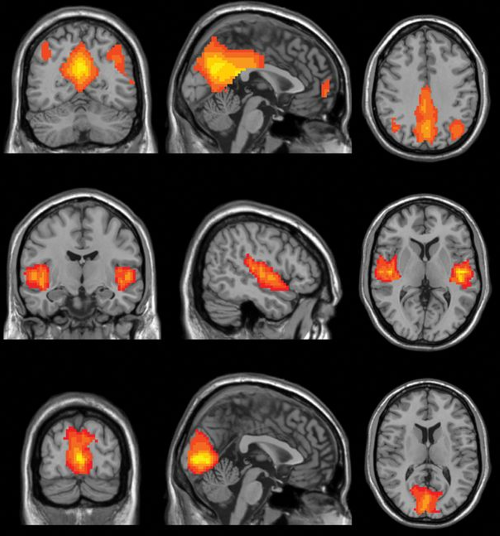

뉴욕 대학(New York University)의 모리아 토마슨(Moriah Thomason) 박사 연구팀은 휴식 상태 기능적 MRI(resting-state functional MRI)를 사용하여 태아의 뇌 연결성을 연구했다. 이 MRI 기술은 특별한 지령을 수행하고 않는 (멍한 상태의) 사람의 뇌에서 부위별 혈류(blood flow)의 차이를 분석한다. 일반적으로 능동적으로 작용하고 있는 뇌의 부위는 혈류량과 산소 소모량이 많음을 이용하는 시각화 기술이다. 어린 시절 외상을 경험한 어머니의 태아는 편도체(amygdala)와 전두엽 피질(frontal cortex)을 포함하는 부위들에서 이미 활성도 차이를 보였다. 이런 뇌 연결성의 차이를 보인 아이들은 위협을 더 민감에 감지했고, 불안 장애를 동반하는 경향을 보였다.

Fig3_resting state fMRI.png 기능적 MRI 기법은 혈류 및 산소 공급의 증가를 인식하여 어느 부분의 뇌가 선택적으로 활성화(activation) 되는지를 밝힌다.